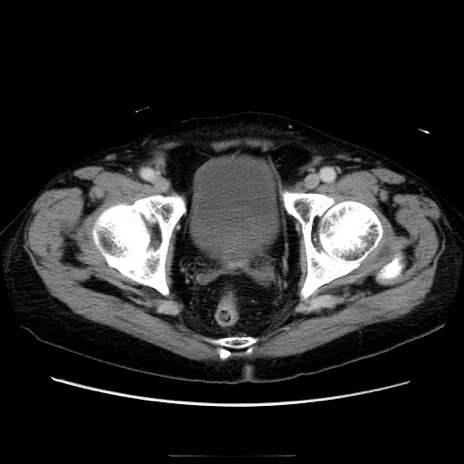

冠状断像

【症例】70歳代男性

【主訴】腹痛

【現病歴】肝硬変・肝細胞癌にてかかりつけの方。約9時間前に食後より腹痛出現。症状が徐々に増悪し、嘔吐出現したため来院。

【既往歴】肝硬変、肝細胞癌(RFA、TACE後)

【身体所見】意識清明、表情苦悶様、BT 36℃、BP 129/78mmHg、P 88bpm、SpO2 97%(RA)、右上腹部から心窩部にかけて圧痛あり、反跳痛なし、筋性防御あり。

【データ】WBC 5800、CRP 0.16